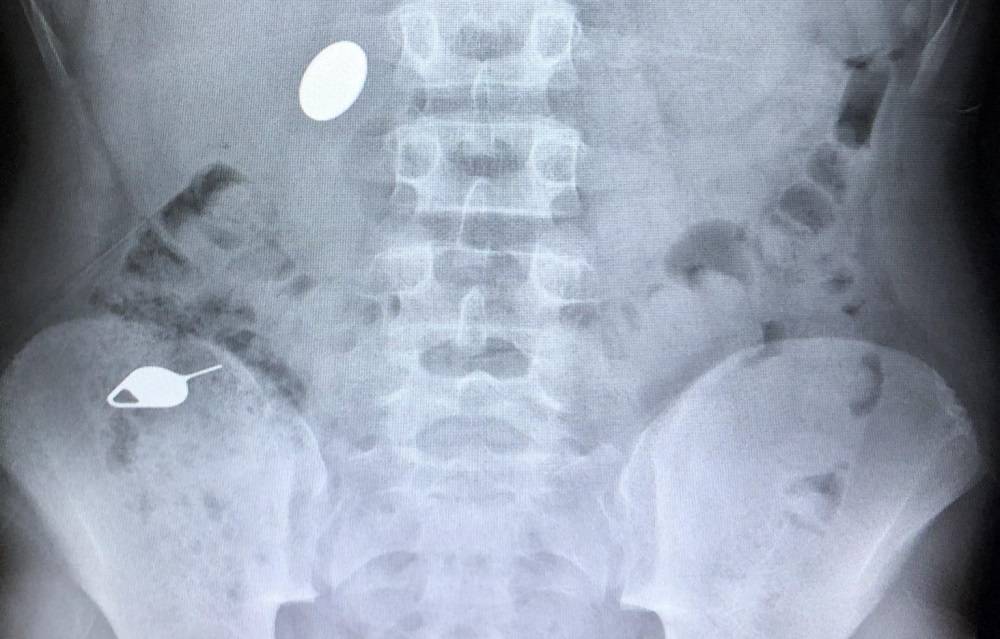

При наличии в просвете желудка металлических предметов необходим динамический рентгенологический контроль за их продвижением по желудочно-кишечному тракту.

- Рентген. Позволяет обнаружить местонахождение монеты;